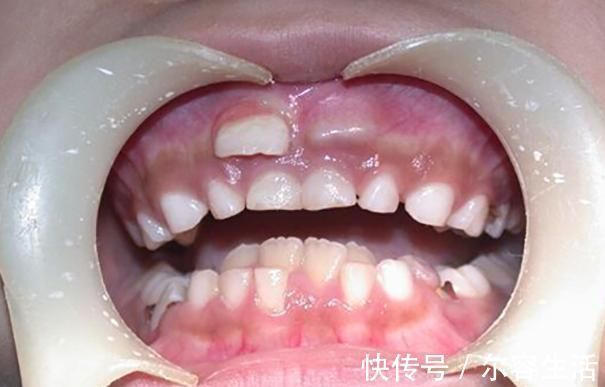

恒牙|越来越多孩子长“双排牙”,与糖果无关,是父母喂养有误区

什么叫做“双排牙”?其实双排牙的主要原因是在换牙期,乳牙滞留,导致恒牙生长受阻,最后恒牙和乳牙并排而立。形成双排牙的主因有很多,糖果的关系并不大,和家长的喂养习惯相关。

一、孩子长出双排牙,一家人跟着着急何丽的女儿今年已经六岁多了,正值换牙时期,可是门牙始终都不松动,父母也没有太在意。可有一天女儿告诉妈妈,自己的门牙里面有两个硬硬的东西。因为门牙没有松动,恒牙没地方长,只能从旁边长出来了。何丽还是没有在意,等着孩子这几天门牙的松动,然后再给孩子拔掉。可是等了近一个多月,孩子的牙齿还是没有松动的迹象。于是何丽察觉到有一些不对劲了,就带着孩子去看了医生。医生说这两年双排牙的孩子越来越多,大部分都是因为饮食习惯不规范造成。

1. 孩子从小不吃硬的食物造成双排牙的极大可能,都是和饮食习惯有关,孩子在添加辅食开始,就是吃泥状食物。随后应该慢慢过渡到颗粒状食物,然后是小块状食物,最后孩子就能独立啃咬完整的食物。但是很多父母担心孩子不吃饭,于是都视线将食物处理好,孩子基本上接触不到稍硬的食材。最后导致乳牙得不到锻炼,就没有松动的迹象。2. 孩子自身的疾病还有些孩子是因为先天性的疾病,或者是继承恒牙出牙无力等等,这些都需要提前看医生,如果乳牙滞留的时间太长,就可以让医生拔出乳牙,让恒牙顺利长出来。

二、长出双排牙的危害1. 影响孩子外貌双排牙的主要危害,还是会影响孩子的外貌长相,孩子的恒牙会伴随一辈子,因为乳牙的滞留,长歪或者长坏了,孩子的整提外貌就会有影响,可能后期还需要花钱矫正,受罪又花钱。而且牙齿长歪了,孩子面部也会发生改变。2. 影响孩子进食双排牙会影响孩子的近视,由于畸形的牙缝存在,孩子咀嚼食物的时候,会产生不适感。而且两张牙齿并立而存,牙龈也会感到不舒服。如果孩子的双排牙影响了进食,那么孩子身体营养就无法跟上了。